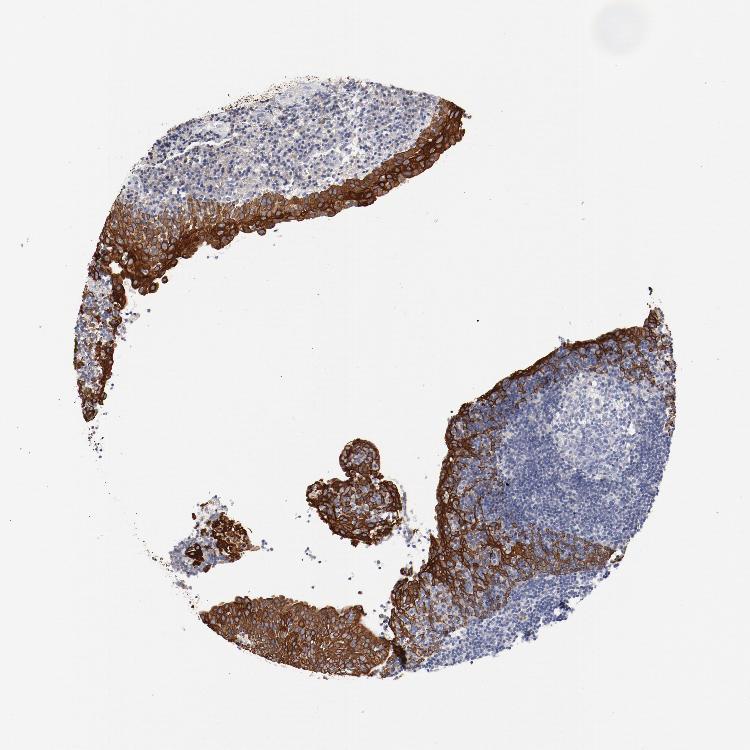

TSPAN6